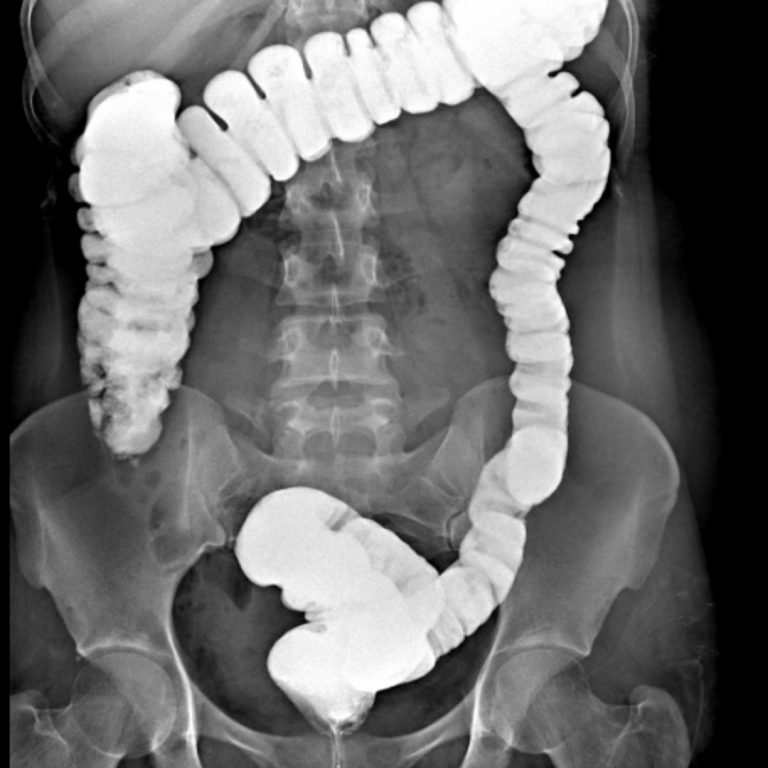

KOLON GRAFİLERİ

İki çeşit baryumlu kolon incelemesi vardır; tek kontrast ve çift kontrast. Kolon kanseri taramasında genellikle çift kontrastlı kolon tetkiki kullanılır.

- Tek Kontrastlı Kolon grafisi

Teknisyen makata bir tüp yerleştirir ve tüpün ucu baryum solüsyonunun olduğu torbaya bağlanır. Verilen baryum yavaşça kolonu sıvar. Bu şekilde kolon görünür hale gelir. Kolon baryum ile doldukça, dışkılama hissi duyulabilir. Baryum vermek için rektuma yerleştirilen tüpün ucunda küçük bir balon vardır. Tüp yerleştirildikten sonra baryum kaçışını engellemek için bu balon şişirilir. Tetkik esnasında masa üzerinde farklı yönlere dönülmesi istenebilir. Böylece verilen baryum tüm kolon segmentlerini doldurur ve kolonun farklı açılardan izlenmesine olanak sağlar. Filmler çekilirken nefesin tutulması istenir.

2- Çift Kontrastlı Kolon grafisi

Bu işlemin tek kontrastlı tetkikten en önemli farkı, kolonun hava ile doldurulmasıdır. Böylece daha kaliteli görüntü elde edilir. Polip gibi daha küçük lezyonlar rahatlıkla seçilebilir. Kolon tetkiki 20-30 dakikada tamamlanmakla birlikte, nadir durumlarda 45 dakikaya kadar çıkabilir. Bu tetkik karında hafif kramplara neden olabilir. Tetkikin bitimi ile şikâyetler sonlanır. Tetkik bitince rektuma yerleştirilen tüp çıkarılır ve kolonun boşaltılması istenir. Tetkiki takip eden birkaç gün dışkı, içeride kalan baryuma bağlı olarak beyaz, gri veya pembe görünümde olabilir. Geride kalan baryum kabızlığa neden olabileceğinden bol miktarda su içilmesi tavsiye olunur.

Rektal yoldan verilen kontrast madde takıntısız çekuma ulaşmış olup ilioçekal bileşke serbesttir. Apendiks vizüalize olmuştur ve normal görünümdedir. Rektum posterior konturu muntazamdır. Presakral mesafe açıktır. Kolon boyunca belirgin haustrasyon artışı mevcuttur. Sigmoid kolon hafif elonge görünümdedir. Kolon lümeninde doluş defekti lehine bulgu saptanmamıştır. Evakuasyon fazında sağ kolon ve hafif sigmoid kolon içinde remnant kontrast madde kalmıştır. Diğer segmentlerdeki kontrast maddenin bulunmaması mukozanın ödemli olabileceğini düşündürmektedir. Çift kontrastlı grafiler ve sağ kolondaki kontrast maddesinin fragmane olduğu dikkati çekmektedir. Bulgular irritable kolonla uyumlu bulunmuştur.